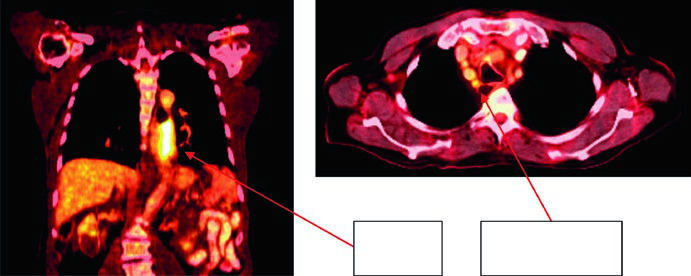

Case 2: Lower Thoracic Adenocarcinoma — 81-Year-Old, uT3N1

An 81-year-old patient with lower thoracic esophageal adenocarcinoma uT3N1. PET showed primary uptake and level 4R paratracheal lymph node. Endoscopy revealed a partially obstructing circumferential adenocarcinoma 31–35 cm from the incisors. EUS confirmed T3 primary disease with suspicious level 4R node. Contours applied a 0.5 cm GTV-to-CTV margin for the 4R node and 3–4 cm inferior coverage. Volumes: brachial plexus (purple), stomach (dark green), esophageal GTV (red), ITV (pink), nodal GTV (light green), CTV (orange), PTV 50.4 Gy (dark blue).